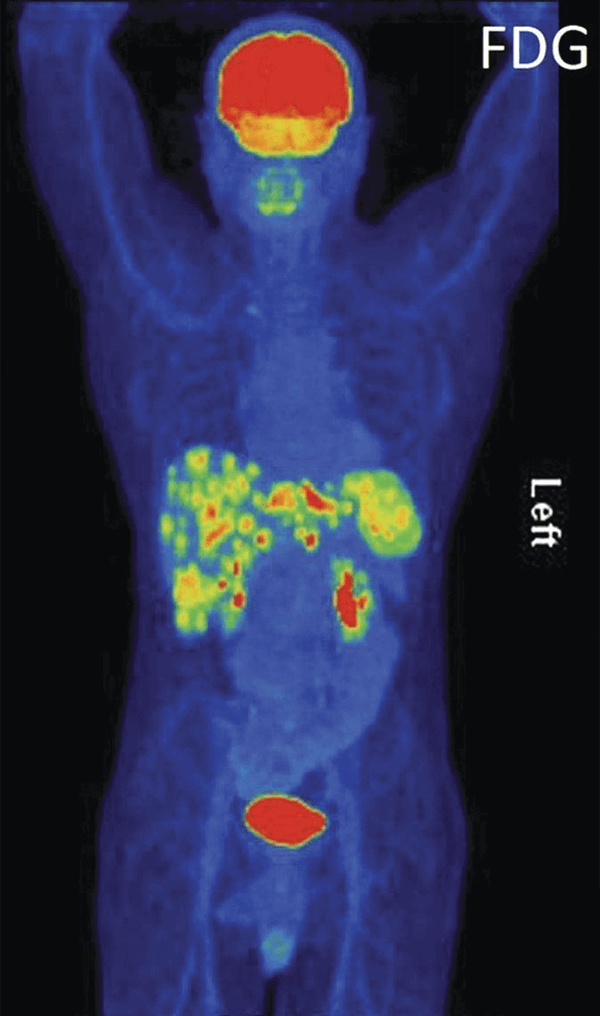

An FDG-PET scan shows a human figure from the front, highlighting areas of metabolic activity in various colors. Bright areas in red and yellow indicate higher activity, particularly in the brain, abdomen, and bladder.

An FDG-PET scan of a patient with gastroesophageal junction cancer.

Credit: Li M, Oxford Medical Case Reports Sept. 2014. doi: 10.1093/omcr/omu041.